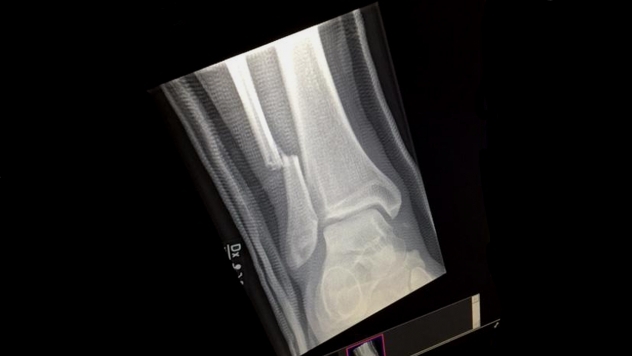

The frontman took a tumble during the Gothenburg set after missing a ramp and falling into the gap between the stage and audience. A statement released by the band has since confirmed that Grohl suffered at least one fracture in his leg.

“While the full extent of Dave’s injuries are still being determined, it was confirmed at a post-show hospital visit that he sustained at least one fracture.

Following the gig, an image of an x-ray was uploaded to Foo Fighters’ official Instagram account with the caption “Thank you Gothenburg. That was amazing.”